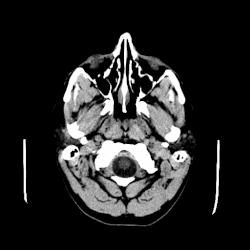

CT scan of a colloid cyst

The diagnostic process typically begins with a medical history workup followed by a medical examination by a physician. Imaging tests, such as CT scans and MRIs, help provide a clearer picture. The physician typically looks for fluid (or other bodily substance) filled sacs to appear in the scans, as is shown in the CT scan of a colloid cyst. A primary health care provider will refer an individual to a neurologist or neurosurgeon for further examination. Other diagnostic methods include radiological examinations and macroscopic examinations. After a diagnosis has been made, immunohistochemistry may be used to differentiate between epithelial cysts and arachnoid cysts.[2] These examinations are useful to get a general idea of possible treatment options, but can be unsatisfactory to diagnose CNS cysts.[3][5] Professionals still do not fully understand how cysts form; however, analyzing the walls of different cyst types, using electron microscopes and light microscopes, has proven to be the best diagnostic tool. This has led to more accurate cyst classification and correct course of action for treatments that are cyst specific. In the past, before imaging scans or tests were available, medical professionals could only diagnose cysts via exploratory surgery.[2]